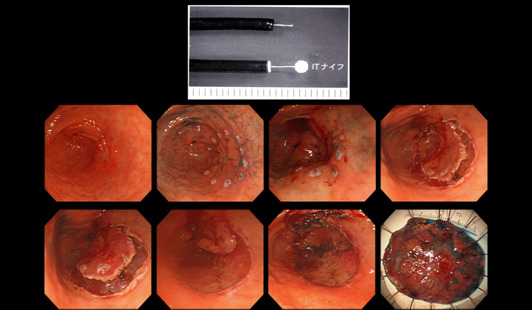

위암, 조기위암 선별

조기 위암은 내시경적 절제술만으로도 완치가 가능한 경우가 많기 때문에 최대한 이른 시기에 발견하는 것이 중요합니다.

육안 소견만으로는 정상 점막과 거의 구별이 안 되는 경우가 많아,

- 색조의 미세한 차이

- 얕은 함몰

- 표면 패턴 변화

등을 근거로 조직검사를 시행합니다. 이 단계에서의 조직검사는 생명 예후와 직결되는 진단 과정입니다.

위내시경 조직검사 과정 설명

조직검사는 내시경 기구 끝에 장착된 겸자를 이용해 점막의 아주 작은 일부를 떼어내는 방식으로 이뤄지며, 통증은 거의 없고 출혈이 발생하더라도 대부분 자연 지혈됩니다.